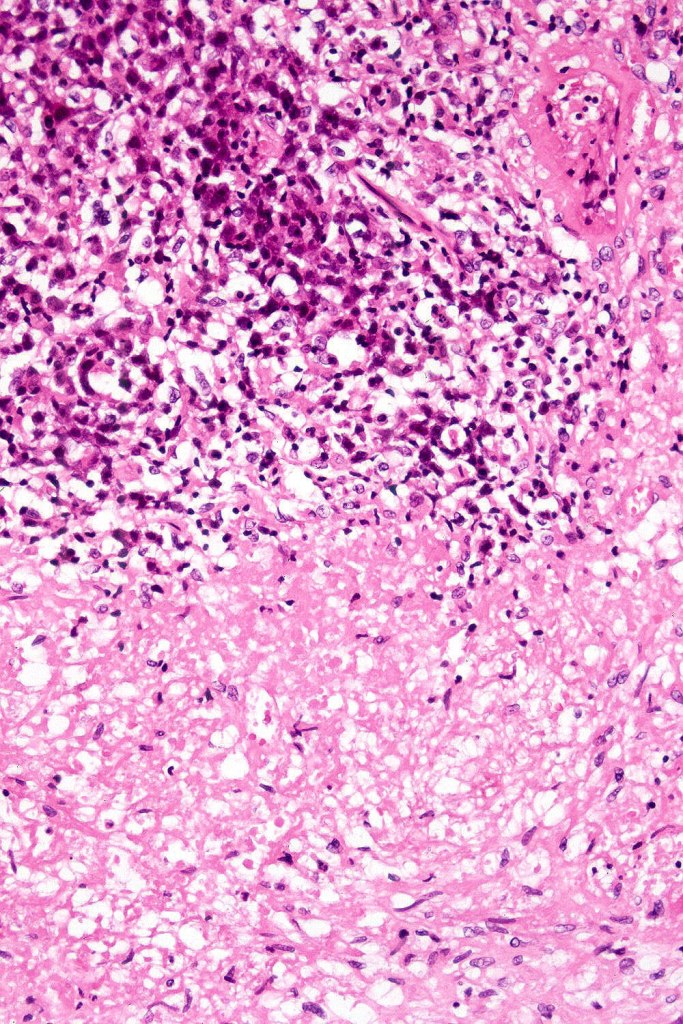

•Angiotropism, angiodestruction, thrombi & coagulative necrosis

•Background inflammatory cells